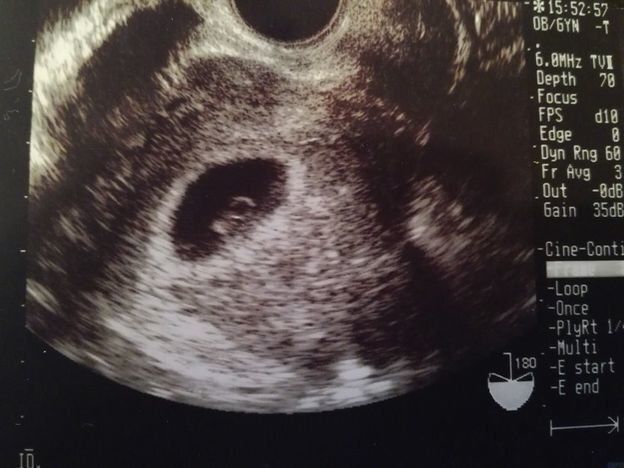

チャーミー小結さんの妊娠5週目のエコー写真

妊娠検査薬で陽性反応が出た翌日、病院を受診して最初に撮ったエコー写真です。この時点で妊娠5週目。初めて見る画像でしたが、モニターに映った瞬間「いる!」と胎芽の入っている胎嚢(袋)が確認できました。